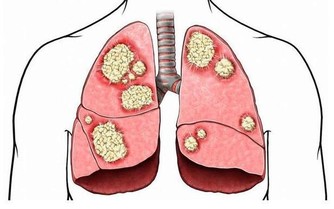

6、可能患癌。手腳冰涼的人容易得癌?這讓很多女性感到震驚,對他們來說,一到冬天老覺得手腳不暖和幾乎已經成為一種「常態」,可是否這樣就真的會被癌症纏上呢?

答案是會!

如果常年手腳冰涼,平時經常覺得疲勞怕冷、打不起精神、唇色較淡、性慾減退,男性經常遺精,女性白帶清稀,則需要提高警惕。

因為這類人就屬於寒性體質,也就是陽虛體質。

穿再厚都覺得冷

而腫瘤的發生和人體的正氣密切相關,長期脾胃虛弱、正氣不足的人更容易被「邪氣」侵犯,有可能發生癌變。正所謂「脾胃虛弱,多有積聚」,因此,有上述困擾的人最好儘早去看醫生,勿等出現明顯信號再就醫。